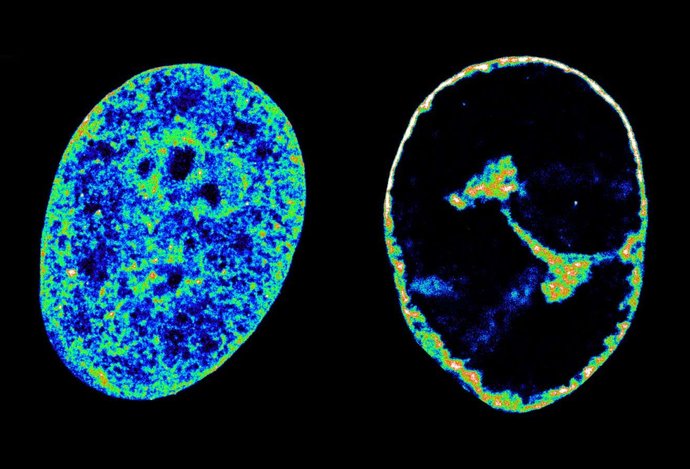

Photo Vírus herpesu dokáže zmeniť náš genóm už za pár hodín od infekcie

Vírus herpesu dokáže zmeniť náš genóm už za pár hodín od infekcie